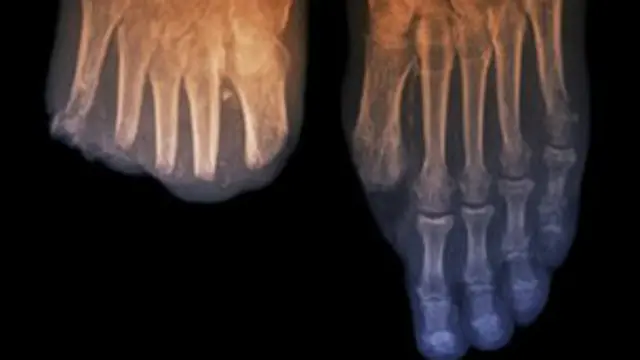

البطء في علاج السكري يزيد احتمال بتر جزء من قدم المصاب

وإذا ما كانت الإصابة بأي من نوعي مرض السكري، 1 أو 2، قد حدثت لفترة طويلة، وخاصة مع عدم الاعتناء بها، فمن الممكن أن يحدث ذلك مضاعفات مثل انخفاض مستوى تدفق الدم إلى الأوعية الدموية بالقدم أو إلحاق ضرر بالأعصاب مما قد يتسبب في انخفاض مستوى الشعور بالقدم.

لذا فإن ذلك قد يزيد من مخاطر إصابة القدم بتقرحات والتهابات قد تؤدي في النهاية إلى تدخل جراحي لبتر جزء منها.

ويشير تقرير صادر بالتعاون مع جمعية المختصين بعلاج القدم والقسم المختص بمرض السكري التابع لهيئة الخدمات الصحية الوطنية البريطانية، يشير إلى أن عمليات بتر القدم تزداد احتماليتها عشرين مرة لدى مرضى السكري أكثر من غيرهم.